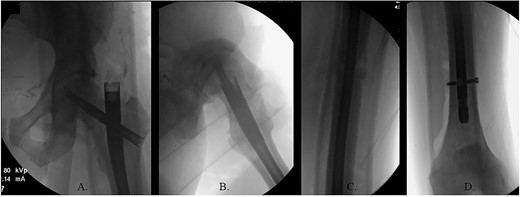

The patient was positioned supine on a fracture table. A guide wire was inserted through a 4-cm surgical incision proximal to the greater trochanter (GT) and was passed through a cannulated awl in a position slightly medial to the tip of the GT on the AP and center on the lateral (Fig. 2B). A (15-mm) entry reamer widened the opening (Fig. 2C). A rigid cannulated reduction rod and forceful malleting allowed the ball-tipped guidewire to cross the close reduced fracture, but too lateral and posterior distally (Fig. 3A and B). The cannulated flexible reamers encountered impassible blastic lesions within the proximal femur (Figs 3C and 5B).

(A) Cannulated awl positioned medial to tip of GT on the AP XR; (B) cannulated awl positioned center of GT on the lateral XR; (C) entry reamer over guide pin on the AP XR.

(A) Ball-tipped guidewire slightly lateral position at the knee on the AP XR; (B) ball-tipped guidewire too posterior at the knee on the lateral XR; (C) flexible reamer within the proximal femur abutting blastic lesions.

(A) Canulated cutter tool creating a new path in the proximal femur; (B) rigid canulated reduction rod directing the guidewire across a reduced fracture held with a proximal bone hook and distal ball spike pusher; (C) center positioned ball-tipped guidewire at the knee on the AP XR; (D) center positioned ball-tipped guidewire at the knee on the lateral XR.